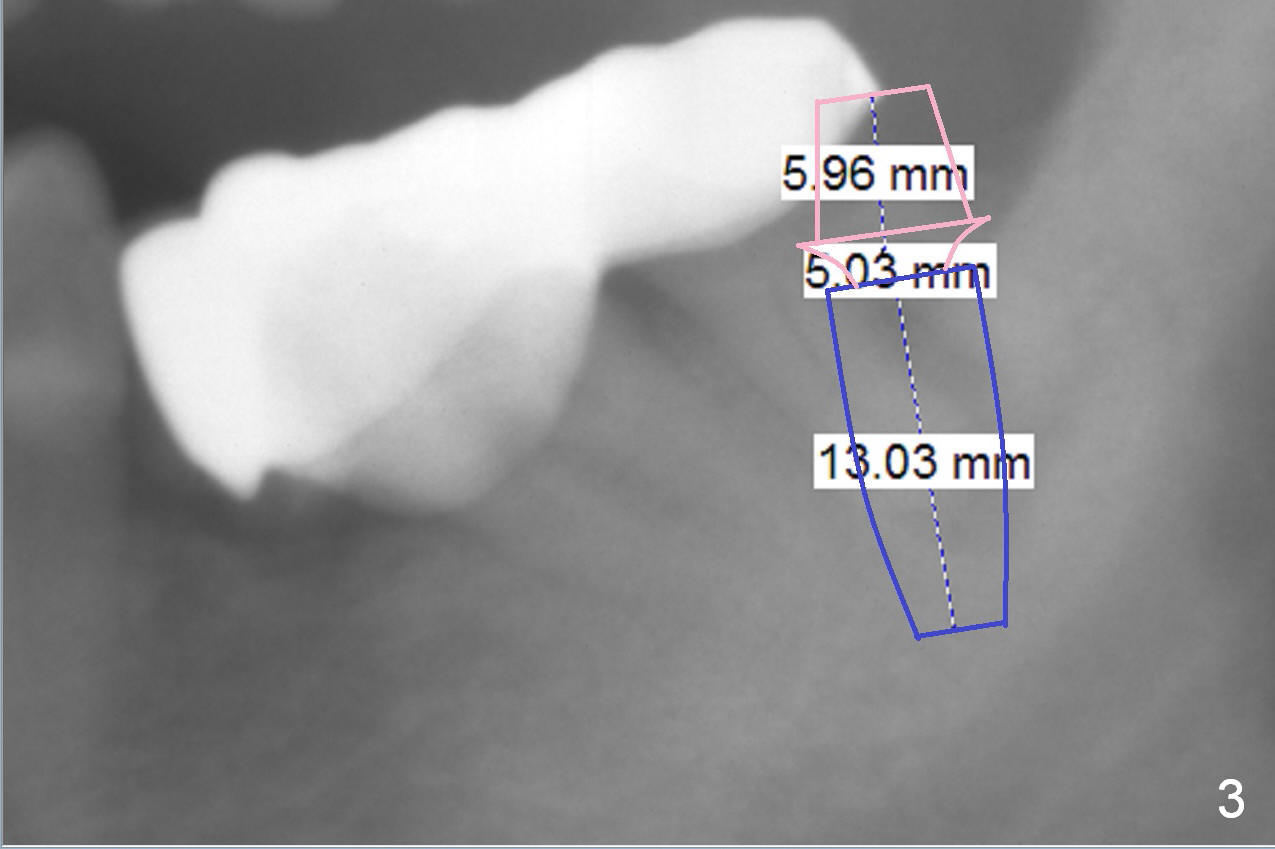

A 82-year-old man has pain in the lower left bridge. There is a buccal apical fistula associated with the tooth #17 (Fig.1). An immediate implant will be placed at #17 after bridge removal (Fig.2,3 blue). Once it osteointegrates, it will be used an anchorage (direct (instead of indirect), most efficient) to upright the tooth #18 (change the longitudinal axis from red line to purple one (Fig.4); white circle: center of resistance (rotation)). Then an implant will be placed at #19 (white rectangle).

Take Alginate impression and keep it moist. It will be used as a stent for temporization later on. After the tooth #17 is extracted with Clindamycin treatment, a FC dummy implant (5x9 mm) will be placed, followed by 6x4(2) mm abutment (Fig.3,4 pink). If there is severe vertical height issue, change to Magicore. Due to schedule conflict, prepare UF for this case instead.